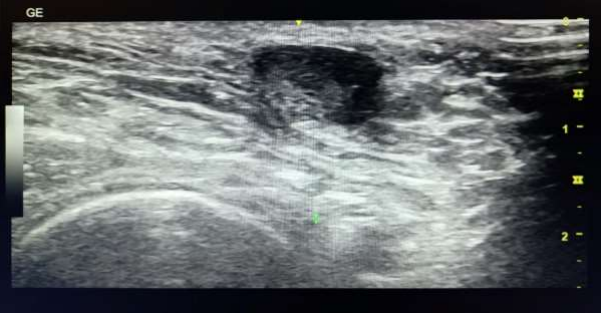

ULTRASONOGAPHY:

FIG1: A well-defined, ovoid thick-walled mixed echoic lesion with internal echoes measuring approximately 1.2 x 0.9 cm with minimal posterior acoustic amplification and surrounding inflammatory alterations in left axilla. The lesion shows lack of internal vascularity on colour Doppler.

An ultrasound revealed a well-defined, ovoid thick-walled mixed echoic lesion with internal echoes measuring approximately 1.2 x 0.9 cm with minimal posterior acoustic amplification and surrounding inflammatory alterations in left axilla. The lesion shows lack of internal vascularity on colour Doppler. A cystic abscess was recommended as the most likely diagnosis based on the sonographic results and suggested histo-pathological correlation for further evaluation. Several foamy macrophages were visible in the fine needle aspiration smears that followed. Granular, proteinaceous material mixed with frothy lipid micelles and occasionally crystalloid substance was also visible in the background. Not a single lymphocyte, atypical or epithelial cells were identified. This ultimately resulted in the diagnosis of galactocele-related supplementary breast tissue.

The imaging on ultrasonography is dependent on the lesion's milk and fat content. These lesions can have posterior acoustic shadowing and range from anechoic to hypoechoic. 5,6  That might not always be the case, though, in general. Sometimes they can seem very substantial due to the high milk content. Furthermore, calcification in an older lesion might occur and be mistaken for cancer. In the same way as mammography.  However, because these lesions exhibit a lack of blood flow, colour doppler imaging may provide a diagnosis indication.